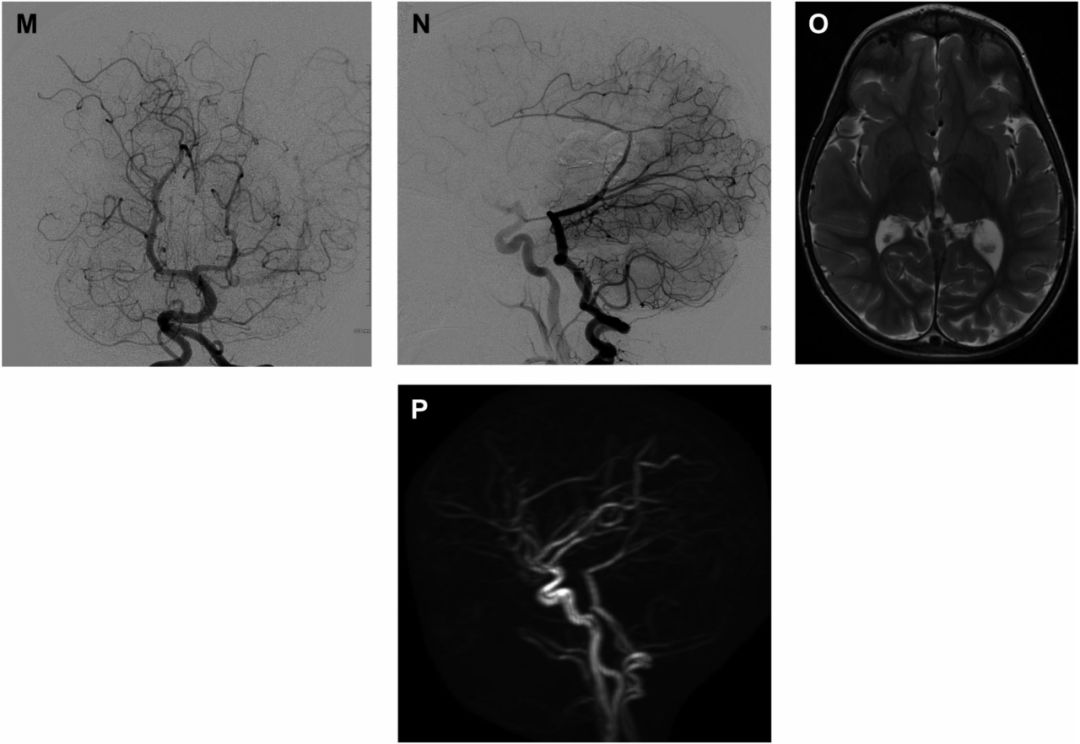

图2 足月患儿,表现为面部静脉扩张、大头畸形、发育迟缓,A-D 患儿10月龄时诊断为VGAM,头颅CT及核磁提示Galen静脉及供血动脉扩张,E-F 左椎动脉造影显示双侧脉络膜后外侧动脉供血,G-H 左侧颈内动脉造影显示脉络膜前动脉供血,静脉期表现为镰状窦狭窄和两侧颈静脉球发育不良,I-J 右侧颈内动脉造影显示大脑前动脉额外供血,向扩张的前脑正中静脉引流K-L 脉络膜前动脉超选造影显示扩张的供血动脉及瘘口。

图3 A-B 大脑前动脉超选示另一供血动脉,C 首次栓塞后注胶,D 残余瘘口,E-F 6个月后二期手术,可见残余瘘口,G-H 二期手术后血供显著减少,I-N 6个月后造影示VGAM完全栓塞,O-P MR示完全栓塞,脑组织发育正常、MRA示正常血管网。